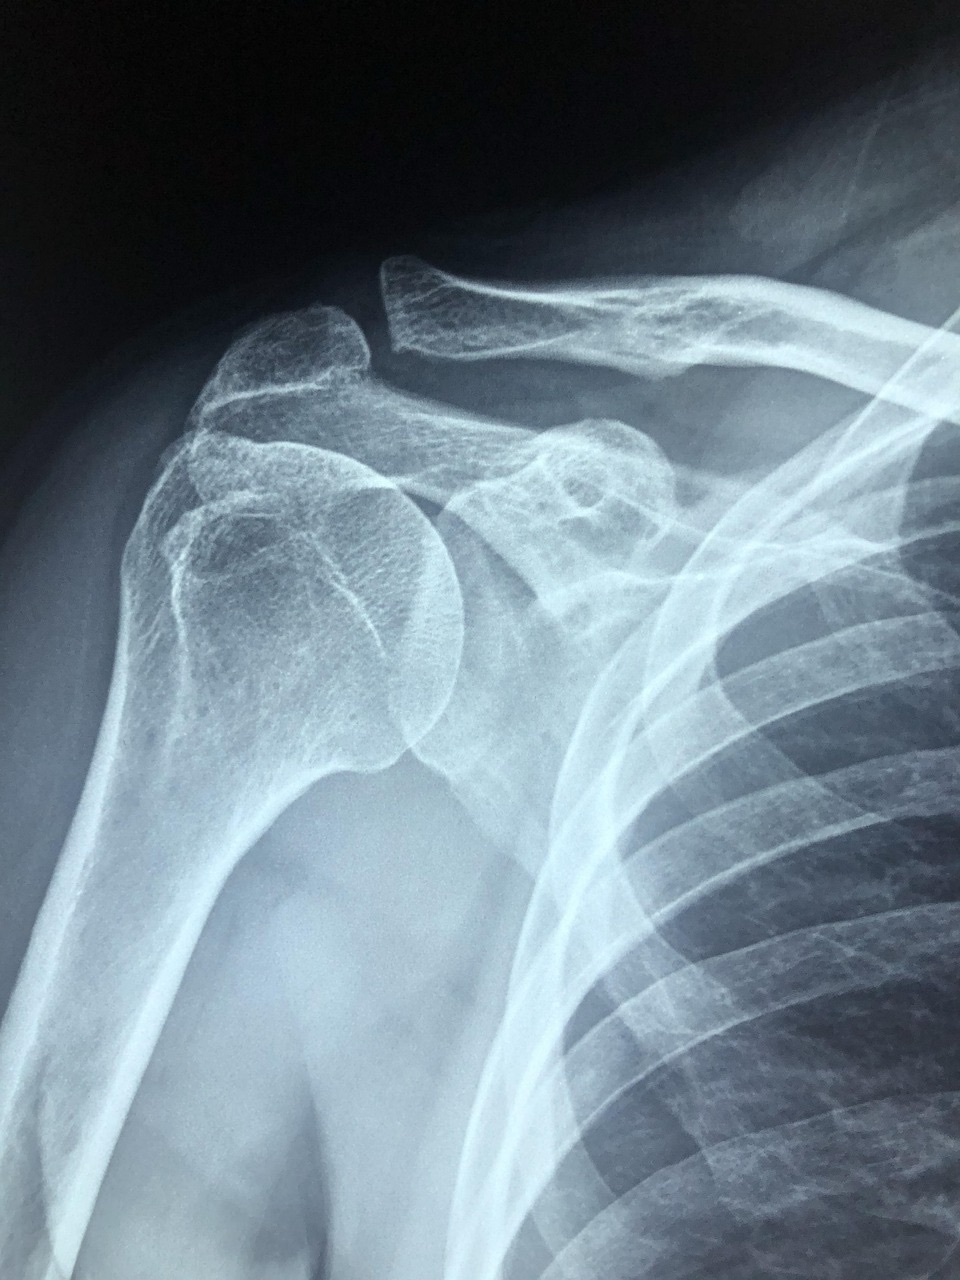

肩痛では、よく肩関節周囲炎(五十肩)がとりあげられる。

肩関節は体の中で最大の可動域を有している関節であり、 解剖学的関節や機能的関節が関与して、可動域を生み出している。

加齢により変性をきたし、外傷や運動によって関節内の炎症・損傷をもたらす。

また、肩関節内には上腕二頭筋長頭腱の走行があり、結節間構表面は上腕横靱帯が覆い、腱鞘のような構造になっている。この部分は、長頭腱が炎症や摩耗変性を生じやすい状態になっていて、このように生じた一連の障害が肩関節周囲炎とされている。